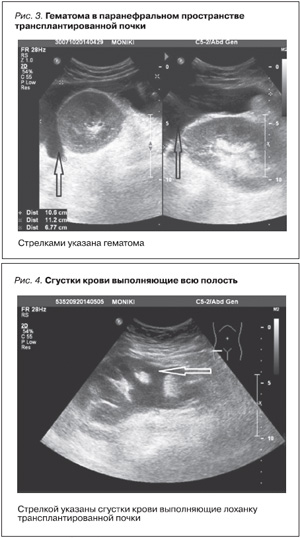

ht="538" style="float: right;" />После биопсии через 50 минут у больной развилась картина геморрагического шока. Макрогематурия. Падение артериального давления до 40/20 мм рт.ст., тахикардия до 120 уд./мин, холодный пот, потеря сознания. Гемоглобин снизился с 93 до 43 г/л, гематокрит – 19,3 г/л. Лейкоциты крови – 12×10`12. Появились выраженные боли в брюшной полости. По данным УЗИ, гематома в области трансплантата (рис. 3).

В лоханке трансплантата сгустки крови, выполняющие всю полость (рис. 4).

В брюшной полости обширные анэхогенные образования – жидкая кровь, заполняющая малый таз (рис. 5).